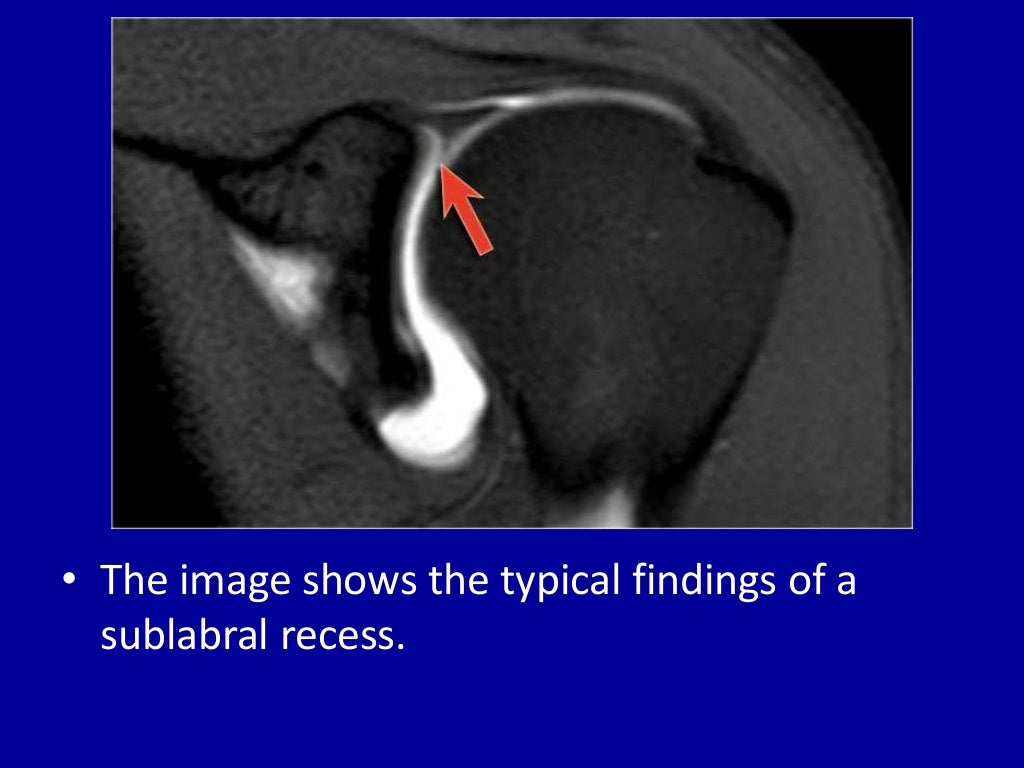

Изменение губы гленоида

Изменение губы гленоида 87 фотографий